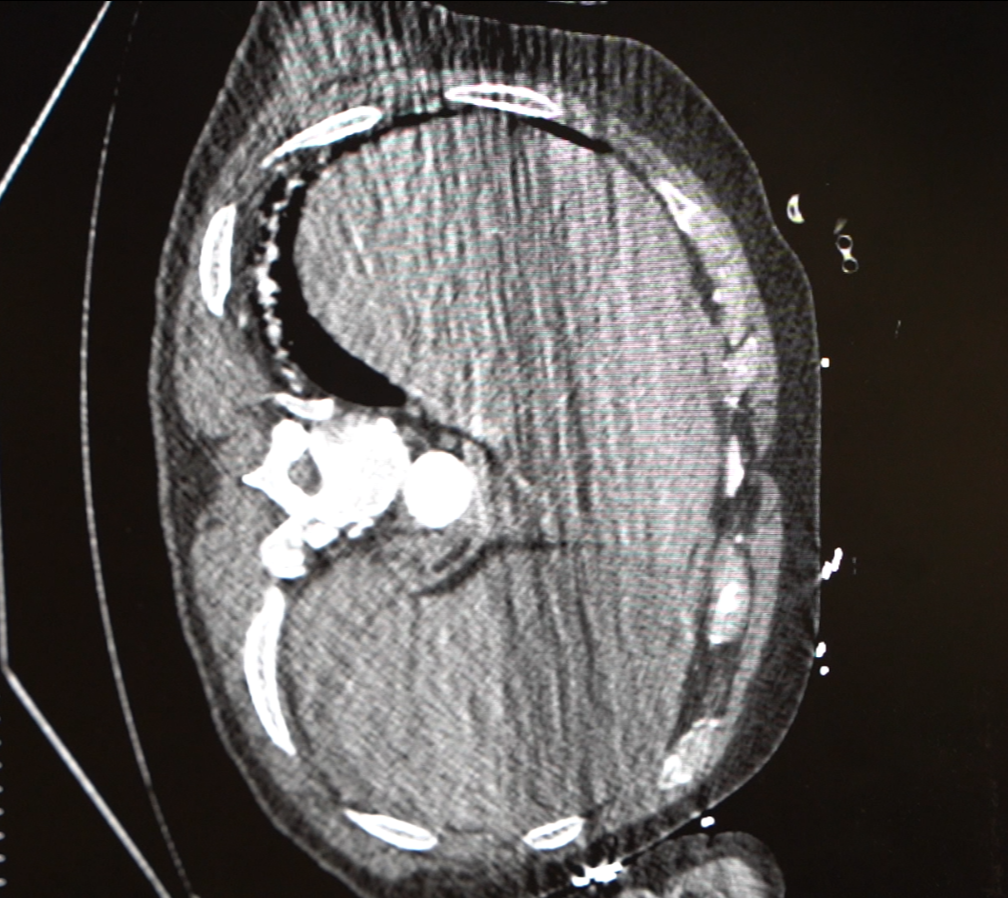

好在经过医务人员63分钟的紧急抢救,章先生终于脱离了生命危险。可是危机并未完全解除。术后的章师傅心率快,血压持续偏低,转入心外ICU,主管医生时乐祥发现,他的心脏因失血过多几乎呈“空泵”状态。

“当时他胸腔里的术前积血还在不断渗出,术后引流血性液体达 1700 毫升,相当于普通人全身血液的1/3。”心外ICU主任赵蕾回忆道。在长达6天的救助与护理之后,章先生终于在这场与死神的拔河中胜利了。